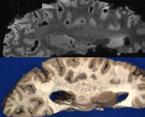

b) a) c) The Tic-Tac-Toe (TTT) radiofrequency head coil for 7T MRI Fig 1: in a), the implemented 16-channel TTT transmit RF coil; in b), the computational RF coil in c), the implemented RF coil with an 32-channel receive insert Fig. 2: The B1+ (magnetic field responsible for spin excitation) field homogeneity is highly degraded at 7T MRI due to a higher operational frequency (~297MHz). The TTT presents a more homogeneous field distribution when compared with the NOVA coil (a commercial coil) [1]. Measured Tic-Tac-Toe Measured Nova coil Regions with low B Simulated Tic-Tac-Toe B + maps in the brain: TTT vs NOVA RF coils TTT coil NOVA coil TTT coil NOVA coil Image comparison with the 32-channel NOVA commercial RF coil a) b) Fig. 3: In a), Turbo spin echo (TSE) sequence using the TTT coil with resolution of 0.4x0.4x2mm. In b), the same TSE sequence acquired with the commercial NOVA coil. In c), FLAIR sequence acquired with TTT coil with resolution of 0.7x0.7x2mm. In d), the same FLAIR sequence acquired with NOVA coil. The arrows point to regions of dark spots in the NOVA coil images and compare with similar regions on the TTT coil images [1]. c) d) High-resolution susceptibility weighted images showing cortical microvessels Fig 4 SWI images acquired at 0 2x0 2x1 5mm resolution In a) an axial slice of the whole brain image acquisition In b) and c), zoomed versions of a), detailing the micro-structures a) b) c) High resolution angiography without contrast agents 380μm a) b) Fig 5: Maximum intensity projection orientation and small vessels detectability isotropic image showing whole brain isotropic acquisition In d), 0 20mm are only detectable at higher resolution

Finger tapping task: activation of Functional MRI a) Diffusion MRI and fiber tracking Post-mortem a) a) b) Fig 7 In a), an structural MPRAGE image acquired at 0 75mm isotropic (skull removed using FSL package) In b), fiber tracking based on DTI acquisition, 64 directions, 1 5mm isotropic resolution The colors are defined for different orientations of the fibers Fig 8: In a), susceptibility weighted images acquired at 0 35mm isotropic, 32 min acquisition time, in a post-mortem brain fixated with formalin In b), a photograph of similar slice in the same brain Table 1: 7T MRI studies conducted at the RF Research Facility at University of Pittsburgh White matter legions (circle): Multiple Sclerosis study Stroke (circle): sickle cell disease study Automatic hippocampus segmentation: Midlife Neurocognitive Lacunar infarct (arrow): depression study White matter hyperintensities (arrows): Healthy Brain aging study (left) and Small Vessels disease in preclinical Alzheimer’s disease study (right) Fig 9: Sample of some studies listed in Table 1 using the developed 16 array (Fig a) There are 4 completed studies and 13 ongoing patient studies with approximated 2 000 patients scheduled FUTURE DIRECTIONS 64-channel Tic-Tac-Toe RF transmit coil for 7T MRI 0 Fig 10: In a), the 64-channel transmit coil computational modeling [2] To improve the field of view of the projector/monitor in fMRI studies, the frontal panels can be removed, resulting in a 56-channel coil In b), one assembled side of the coil In c), simulated B1+ field distribution: for an 8kW power amplifier capabilities (default in older 7T MRI scanners) a homogeneity (measured by the coefficient of variationCV) of 15 2% is achieved in the brain For an 16 kW power amplifier (available for the recently FDA approved Siemens 7T MAGNETOM Terra), an CV of 10 6% can be achieved in the brain 16 kW power amplifier: 8 kW power amplifier: a) b) c) max